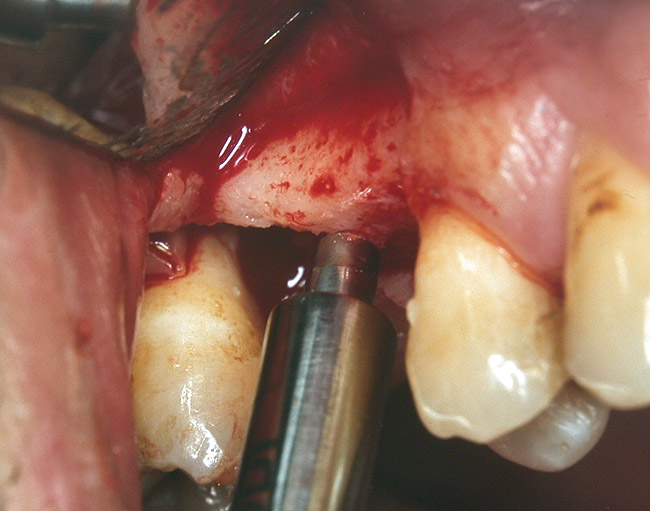

At the time of surgery, the tooth was extracted without harvesting any mucosal flap because the implant site was prepared by means of a pilot drill bur (Figure 13) and alternating osteotomes (Figure 14A and Figure 14B). The implant was positioned and showed primary stability. The implant was loaded 2 days after surgery. Then, splinted PFM crowns supported by custom gold abutments were delivered. At 6 months posttreatment, the radiograph revealed no bone resorption and the clinical result was optimal (Figure 15A and Figure 15B).

Figure 13  The drill bur was used to start the implant site preparation.

Figure 13